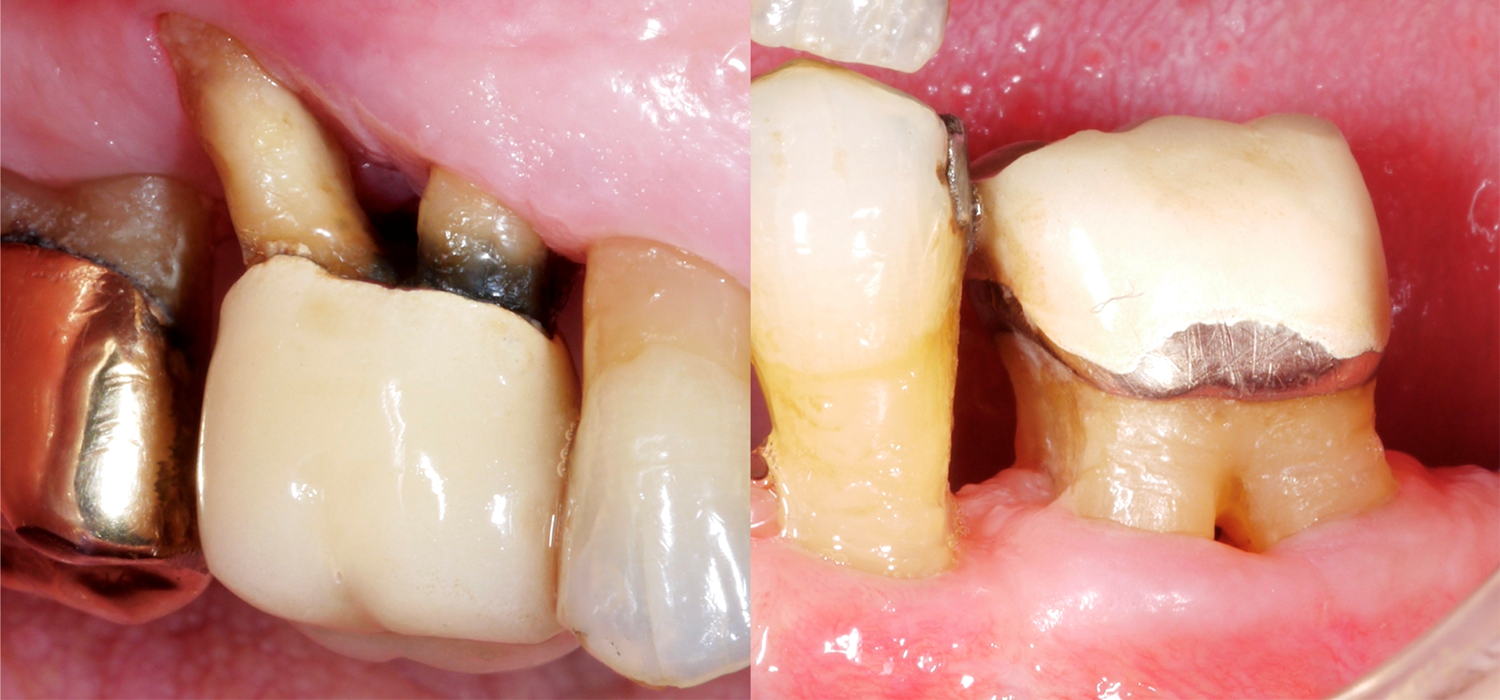

When it comes to teeth, those with multiple roots are, of course, often much more difficult to treat, especially if they present furcation defects. Why is the furcation area so challenging? In comparison to single-rooted teeth, access for mechanical cleaning of the root surface is much more difficult, the furcation entrance can often be very small/narrow, and there may also be further anatomical particularities, such as enamel projections.

A recently published study from Frankfurt (Eickholz 2021) specifically looked at teeth with a through-and-through furcation defect. They studied a total of 265 teeth with a through-and-through furcation defect in 160 patients; all patients had been receiving periodontal maintenance treatment for at least five years. We should take the following important points into account based on this data: